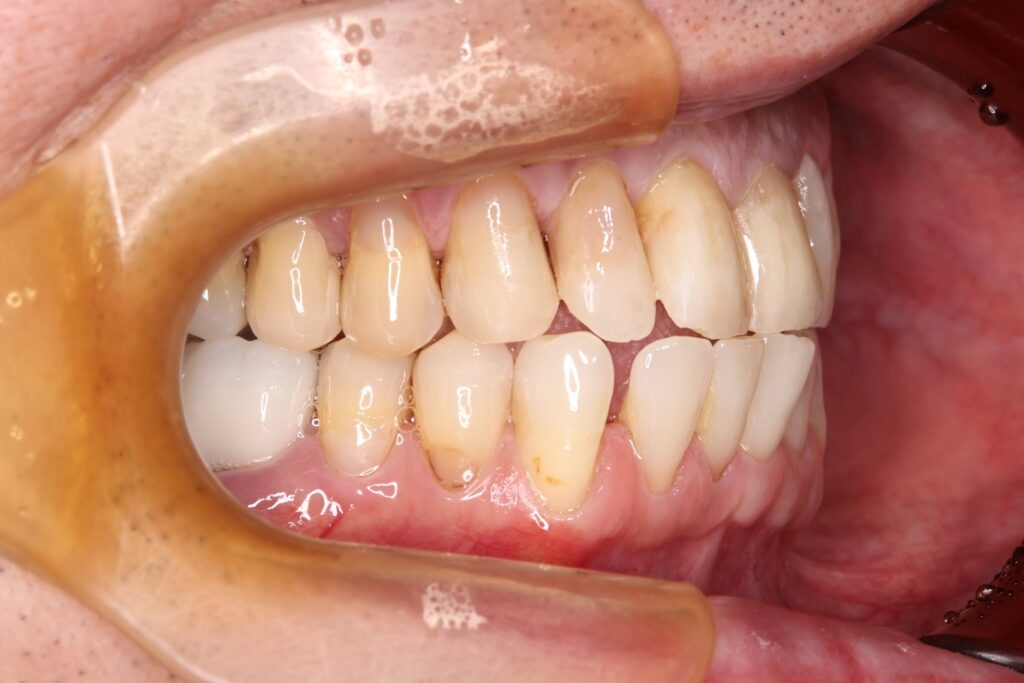

初診時の口腔内の状態:

お口全体に虫歯や歯周病の原因となるプラーク(歯垢)が多く付着していました。右上奥歯は重度の虫歯で歯冠部(歯の頭)が失われており、左下奥歯は過去の治療箇所から細菌が入り込み、根の先に炎症が起きている状態でした。

また、左右の奥歯にはWSD(楔状欠損)があり、知覚過敏も見られました。